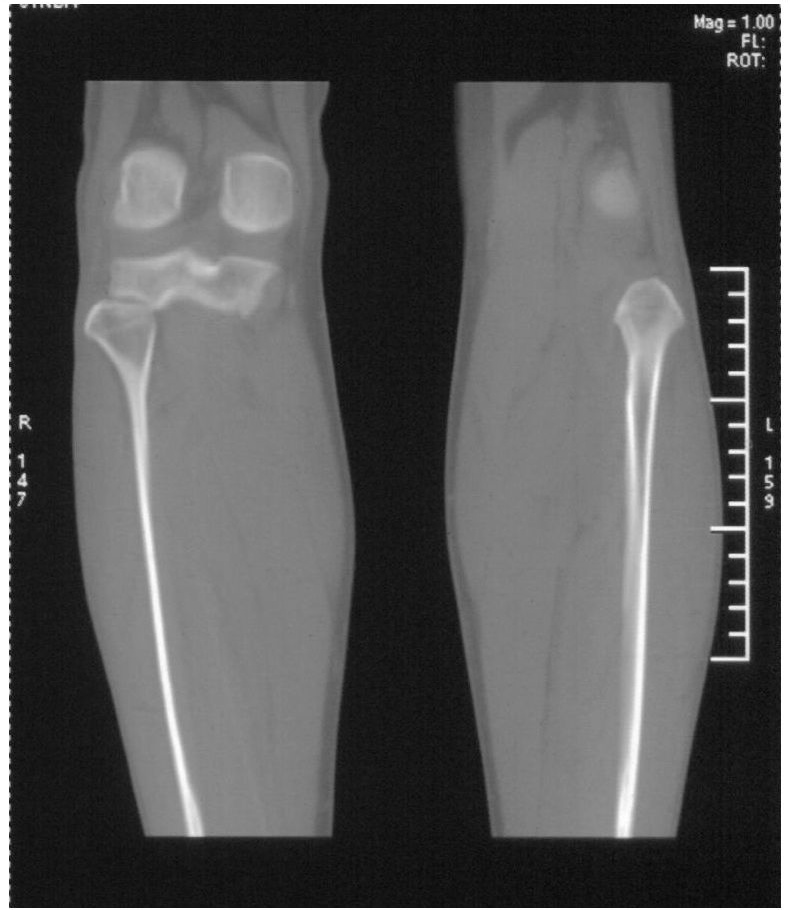

男,42岁。4个月前钢筋钝伤右侧小腿部,当时因无明显外伤,未引起重视。一周后因受伤腿部疼痛,发现肿胀,随后到当地医院进行检查(2008年4月16日)。因未发现骨质异常未引起重视,仅仅进行口服抗生素治疗处理。经过一段时间治疗但未见明显治疗效果在5月29日又进行x线检查,发现有胫骨密度上段密度增高,又进行抗炎治疗,仍未见效果。又在7月3日进行x线检查,仍然报告有胫骨上端密度增高,并建议ct检查。以下是相关检查结果:

髓腔密度呈絮状增高,胫骨上端内侧可见层状骨膜反应,考虑骨髓炎.

髓腔密度呈絮状增高,胫骨上端内侧可见层状骨膜反应,肌间隙模糊,考虑骨髓炎.